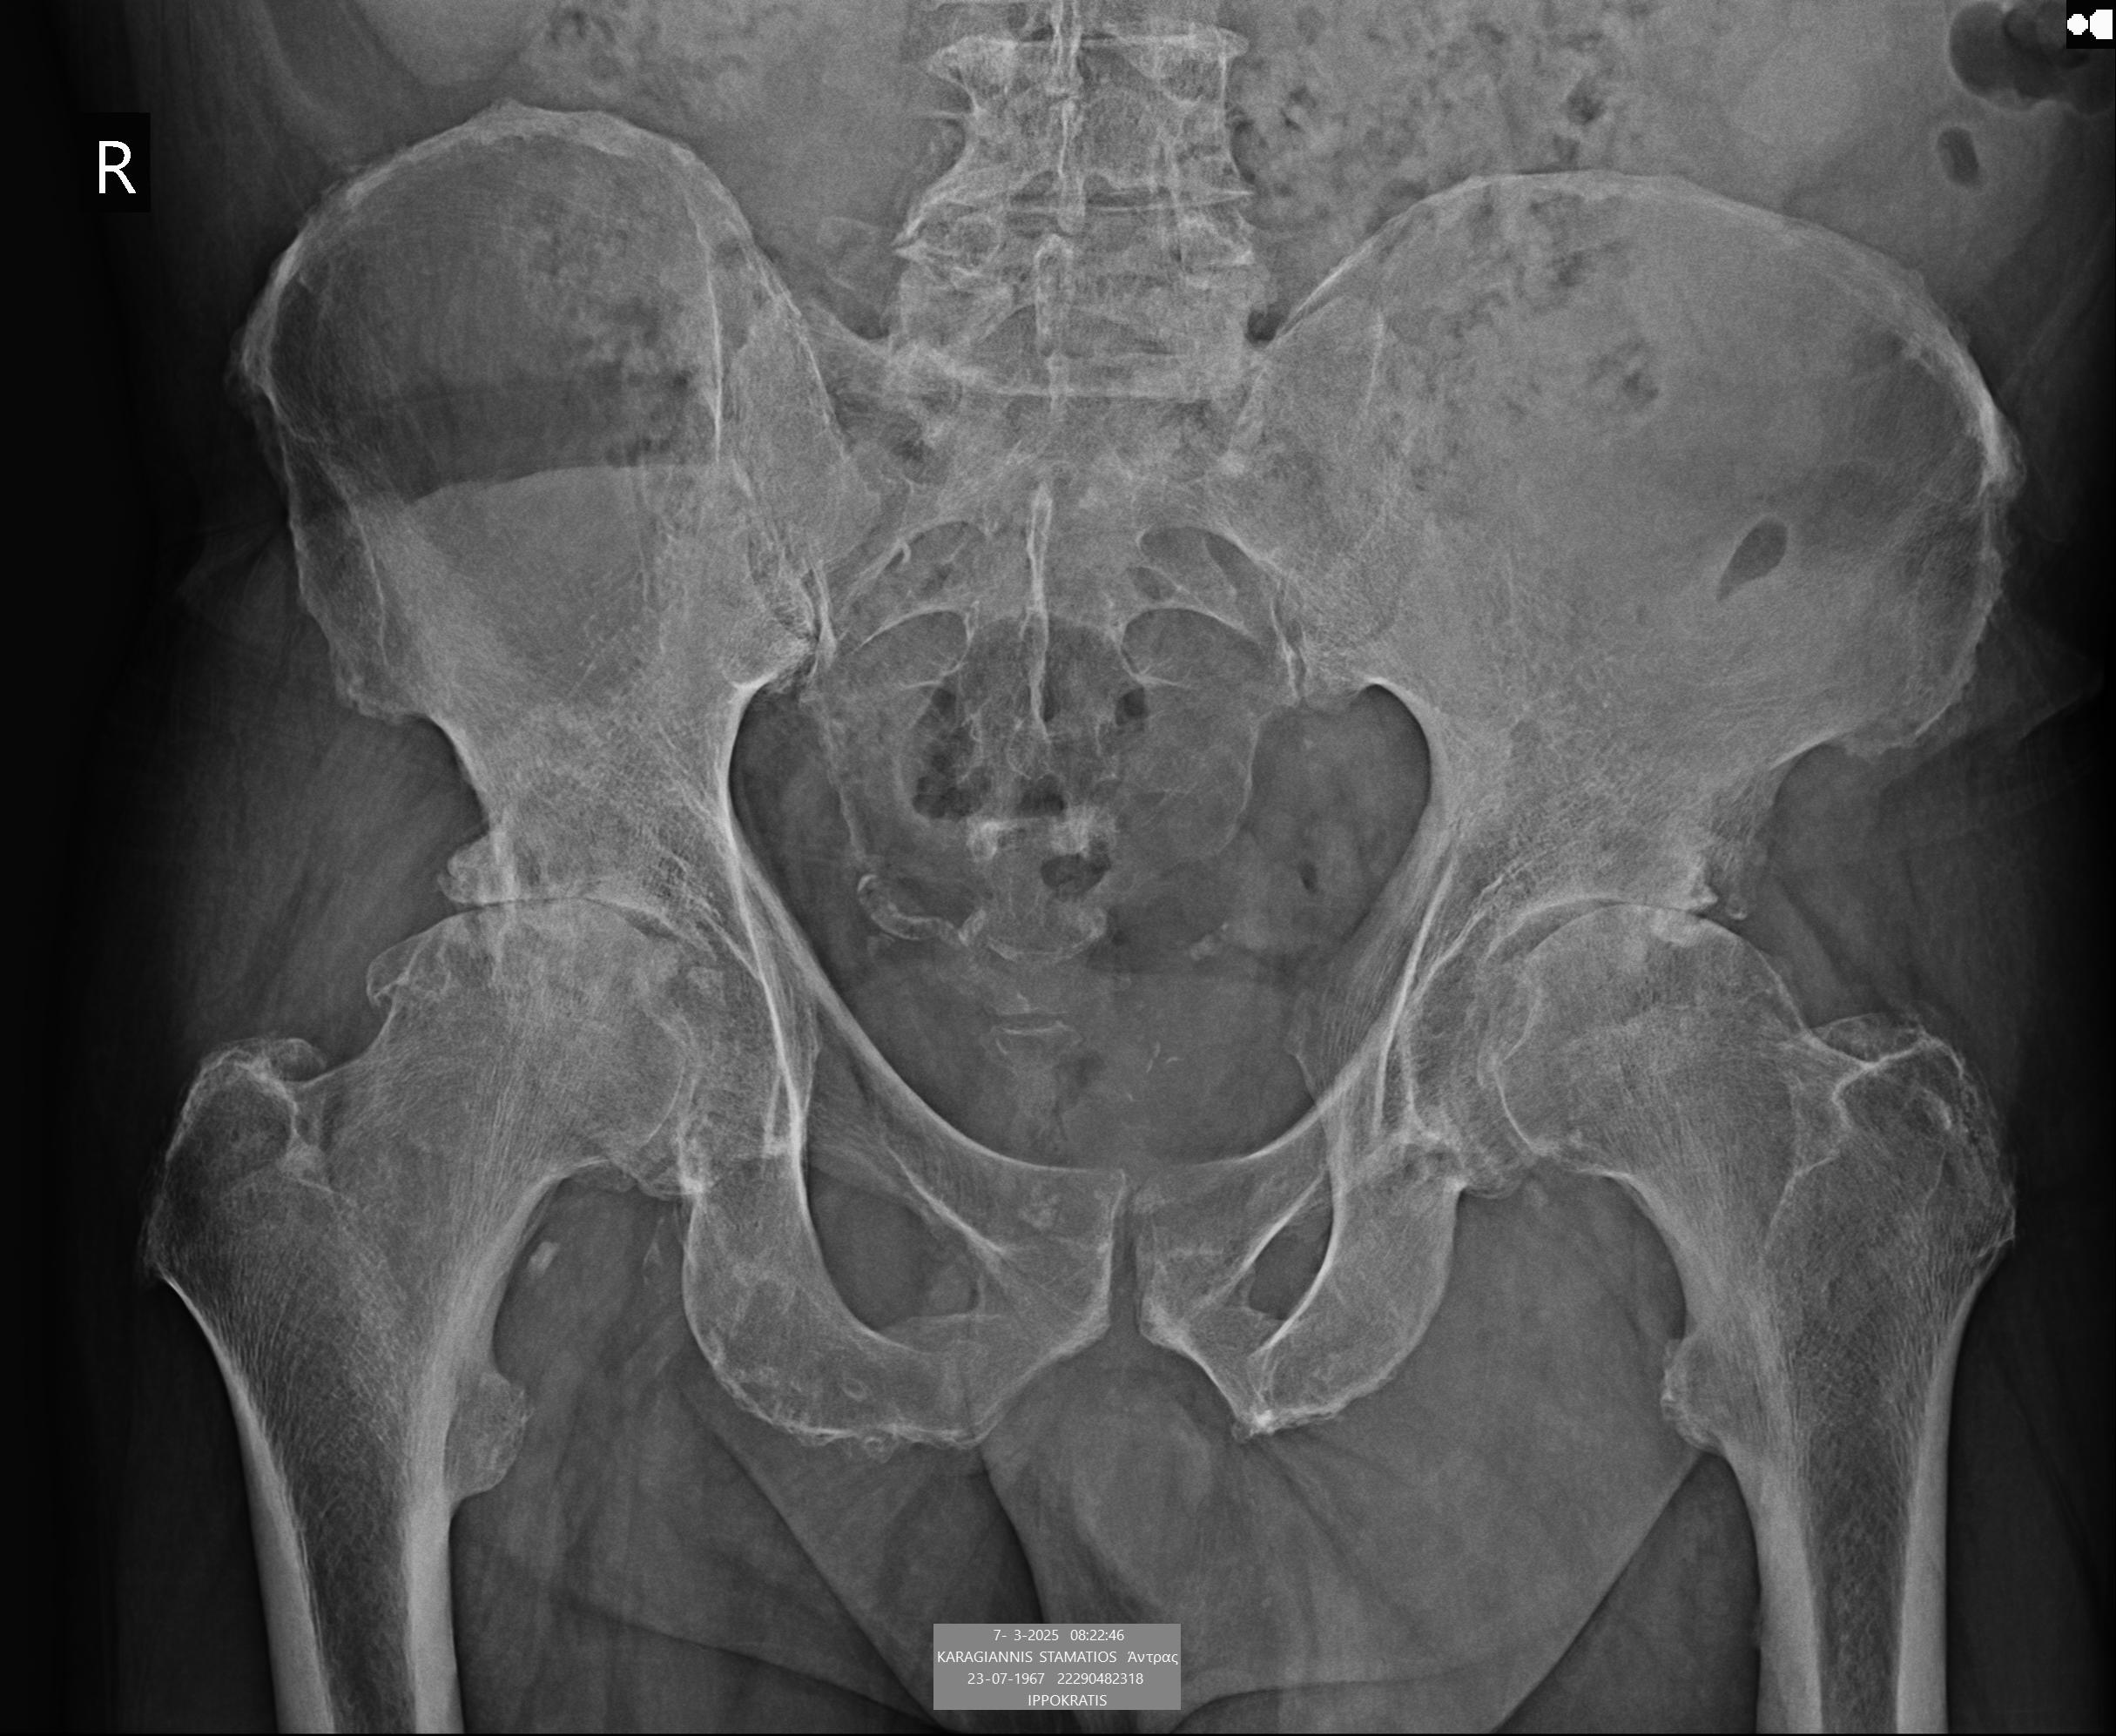

Η απλή ακτινογραφία είναι πάντοτε η πρώτη εξέταση. Δείχνει με σαφήνεια τη στένωση του μεσάρθριου διαστήματος, την παρουσία οστεοφύτων, την παραμόρφωση της κεφαλής του μηριαίου και πιθανές υποχόνδριες κύστεις. (εικόνα 4)

Είναι οικονομική, γρήγορη και παρέχει άμεσα τις βασικές πληροφορίες.

Στην ακτινογραφία παρατηρείται πλήρης συνήθως εξαφάνιση του αρθρικού διαστήματος, παραμόρφωση της κεφαλής του μηριαίου και εκτεταμένα οστεόφυτα.

Στην εικόνα 6 απεικονίζεται η ακτινογραφία ασθενούς, από το αρχείο μας, με προχωρημένη αρθρίτιτδα και των δύο ισχίων. (Ο ασθενής υποβλήθηκε την ίδια μέρα σε ταυτόχρονη αρθροπλαστική AMIS και στα δύο ισχία του)